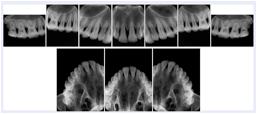

2. A patient requests cosmetic surgery to enhance their facial appearance. The case requires consultation between an orthodontist in New York and an oral surgeon in California. The cephalometric series of 2D projections constructed from the volumetric CT data that is used for the discussion is arranged by a Structured Display for transfer between the two practitioners.

Cephalometric Series Structured Display

Figure OO-2. Cephalometric Series Structured Display